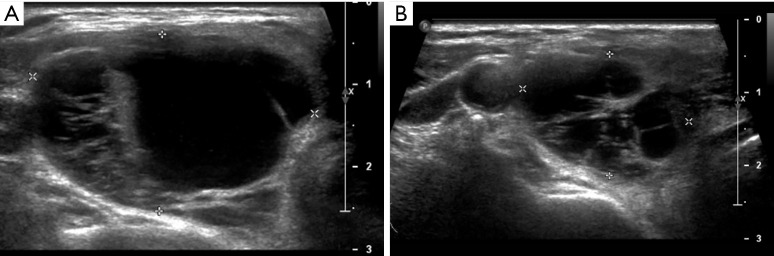

Case description: We report a female patient diagnosed with primary hyperparathyroidism, presenting with a PTH level of 192 pmol/L (1.8-8 pmol/L) and severe hypercalcemia. Preoperative 99mTc-MIBI imaging localized a left inferior hyperfunctioning parathyroid gland. Excision of the left parathyroid gland did not yield the expected fall in intraoperative parathyroid hormone (IOPTH) levels. However, an earlier ultrasound scan detected a concomitant right thyroid cyst. The cyst fluid was aspirated and sent for IOPTH assay, which revealed a high PTH level (1,060 pmol/L). The patient subsequently underwent a right hemithyroidectomy. IOPTH levels showed a 78% reduction post-surgery. Histology of the right lobe confirmed an intrathyroidal right PC amid benign thyroid follicles. The serum PTH level normalized to 1.1 pmol/L postoperatively. The patient was discharged in good condition and is undergoing annual ultrasound and PTH level surveillance.